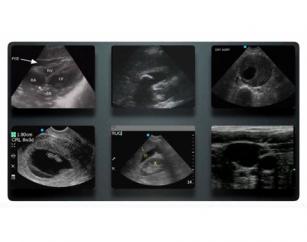

Performing a renal study in point-of-care ultrasound (POCUS) 7th Feb 2017 - Viveta Lobo, MD After watching this video, you will know how to acquire and interpret normal images of the kidneys, ureters and bladder ...

Understanding point-of-care ultrasound basics 19th Jan 2017 - Viveta Lobo, MD When should POCUS be used and how? In this video, you'll learn about some common applications of POCUS and the one ...